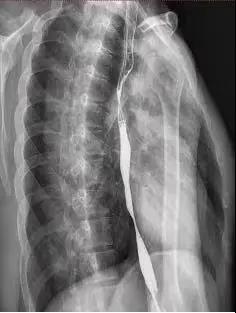

再去医院复诊时,影像结果显示,他的食管中下端居然细成了一根“线”:食管内壁结了厚厚的痂,几乎塞满整个食管,导致食物无法顺利通过,中间最宽的地方只有3毫米左右的空间。

小蔡的中下端食管细成一条线

因食管“结痂”导致吞咽不畅